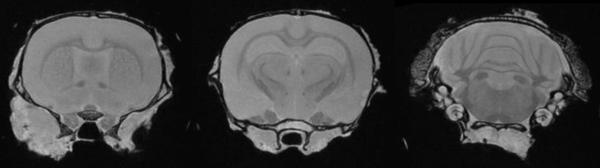

Ex Vivo Imaging: Ex vivo imaging can produce high-resolution images of the rat brain providing excellent delineation of brain regions.

Ex-Vivo Imaging: Ex vivo imaging can produce high-resolution images of the rat brain, providing excellent delineation of brain regions. Image Credit: Scintica Instrumentation Inc

Ex vivo imaging can produce high-resolution images of the rat brain providing excellent delineation of brain regions.

Ex vivo imaging can produce high-resolution images of the rat brain providing excellent delineation of brain regions. Image Credit: Scintica Instrumentation Inc